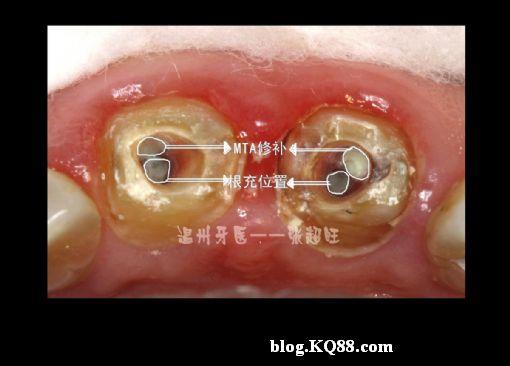

根管侧穿mta修补后再修复张超旺

根管侧穿图片